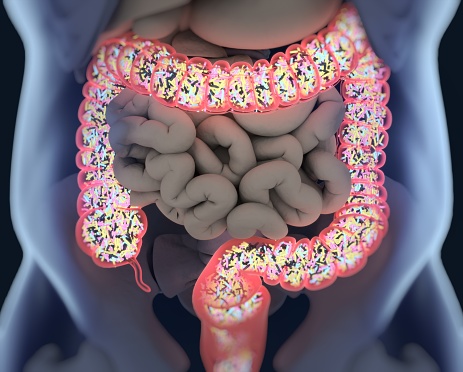

Your body is a diverse network of cells that all work together to create life. However, this would be impossible to do alone, as we harbor millions of bacteria in our intestinal system that help us break down and digest food. Called “probiotics,” these organisms have been found to not only relieve gastrointestinal upset but ...click here to read more